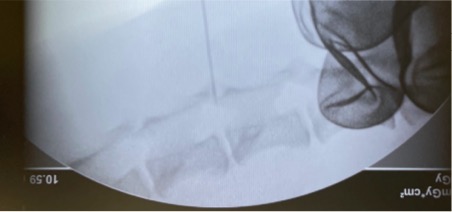

MRI所見より髄膜炎が疑われたため、腰部より髄液採取を実施しました。画像はCアームという画像検査機器を用いて針を骨の隙間から挿入しているところです。正常な髄液は細胞成分の含まれない水に近い液体ですが、髄膜炎などでは髄液中の白血球細胞数やタンパク質が増加したりと色々な変化を伴います。

Cアーム撮影下での髄液採取